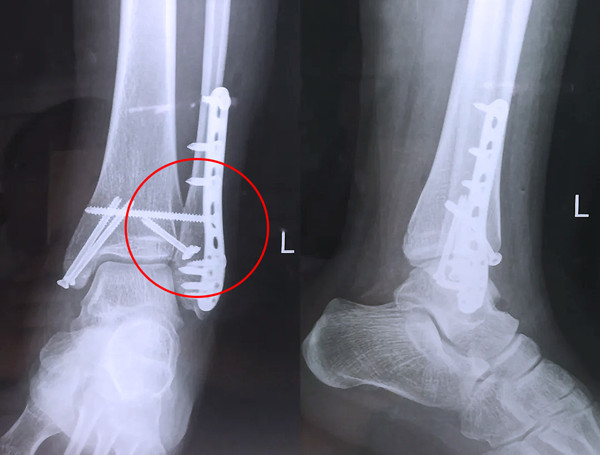

【醫(yī)療科普】Pilon骨折

有一種特殊類型的踝關(guān)節(jié)骨折,可能在X影像平片上就不能顯示出來,它就是脛骨的關(guān)節(jié)面往里塌陷,我們又稱之為叫“Pilon骨折”。當(dāng)它往里塌陷后,我們?cè)赬影像平片上可能看不出來它是否塌陷,但是我們?cè)贑T上可以360°看到踝關(guān)節(jié)的影像,這樣就可以看出患者是否存在踝關(guān)節(jié)塌陷的骨折。同樣道理,我們?cè)谧鯬ilon骨折手術(shù)的時(shí)候,普通二維的X影像并不能判斷我們手術(shù)復(fù)位情況的好壞,這個(gè)時(shí)候如果醫(yī)生手上有能夠照三維影像的工具,那么對(duì)于醫(yī)生的準(zhǔn)確手術(shù)是非常有好處的。